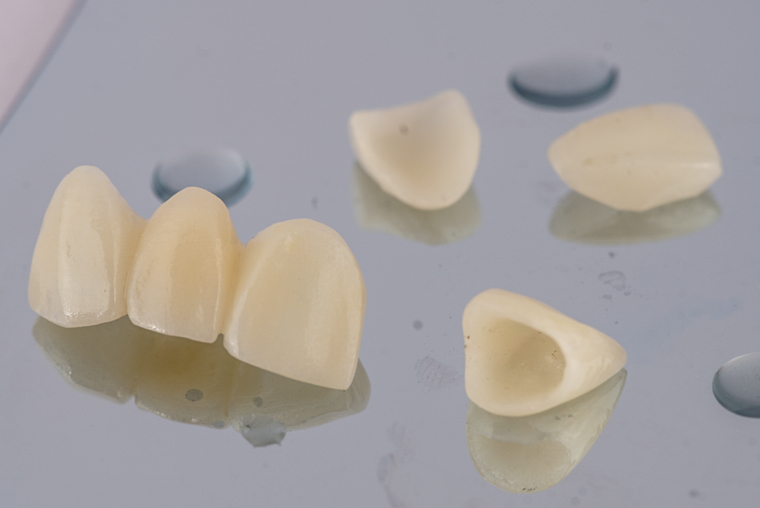

ทำการบันทึกการสบฟัน และส่งแบบสบฟันเพื่อเตรียมชิ้นงานเซรามิก

แกะขี้ผึ้ง(wax mock up)เพื่อดูรูปร่างฟันก่อนขึ้นชิ้นงานเซรามิก

ชิ้นงานเซรามิกที่เสร็จสมบูรณ์แล้ว ในหลายๆมุม

เมื่อได้ชิ้นงานมาแล้วทำการตรวจชิ้นงานในแบบจำลอง ดูการสบฟัน ก่อนนำมาใส่ในคนไข้ต่อไป